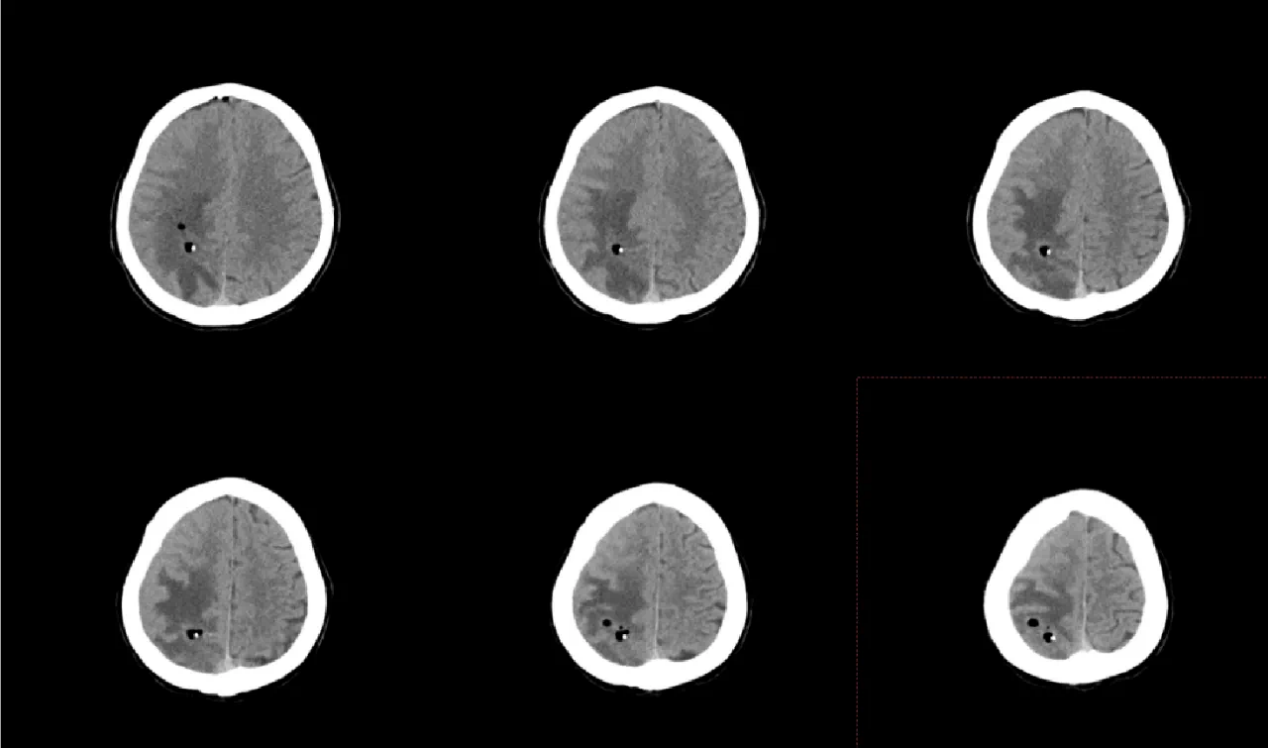

面对李女士的病情,神经外科团队经过反复讨论,决定采用机器人辅助实时可视化抽吸微创手术。手术前,团队通过3D影像重建技术,为李女士的脑部构建了精准的三维模型,清晰标注出脓肿的大小、形态以及与周围血管、神经的位置关系。手术机器人则根据这些数据,自动规划出最优穿刺路径,误差可控制在0.5毫米以内。

在机器人“导航”系统的引导下,神经外科主任王文波主任医师手持穿刺针,沿着预设路径稳步推进。术中,实时影像系统如同“透视眼”,清晰显示穿刺针的位置和脓肿内部情况,医生可以动态观察抽吸过程,确保每一步操作都精准无误。传统开颅手术需要打开十几厘米的切口,创伤大、恢复慢,还可能引发感染。而机器人辅助手术不仅创伤小,还能最大限度减少对正常脑组织的干扰。术后李女士肢体功能逐渐恢复,一周后完全恢复。